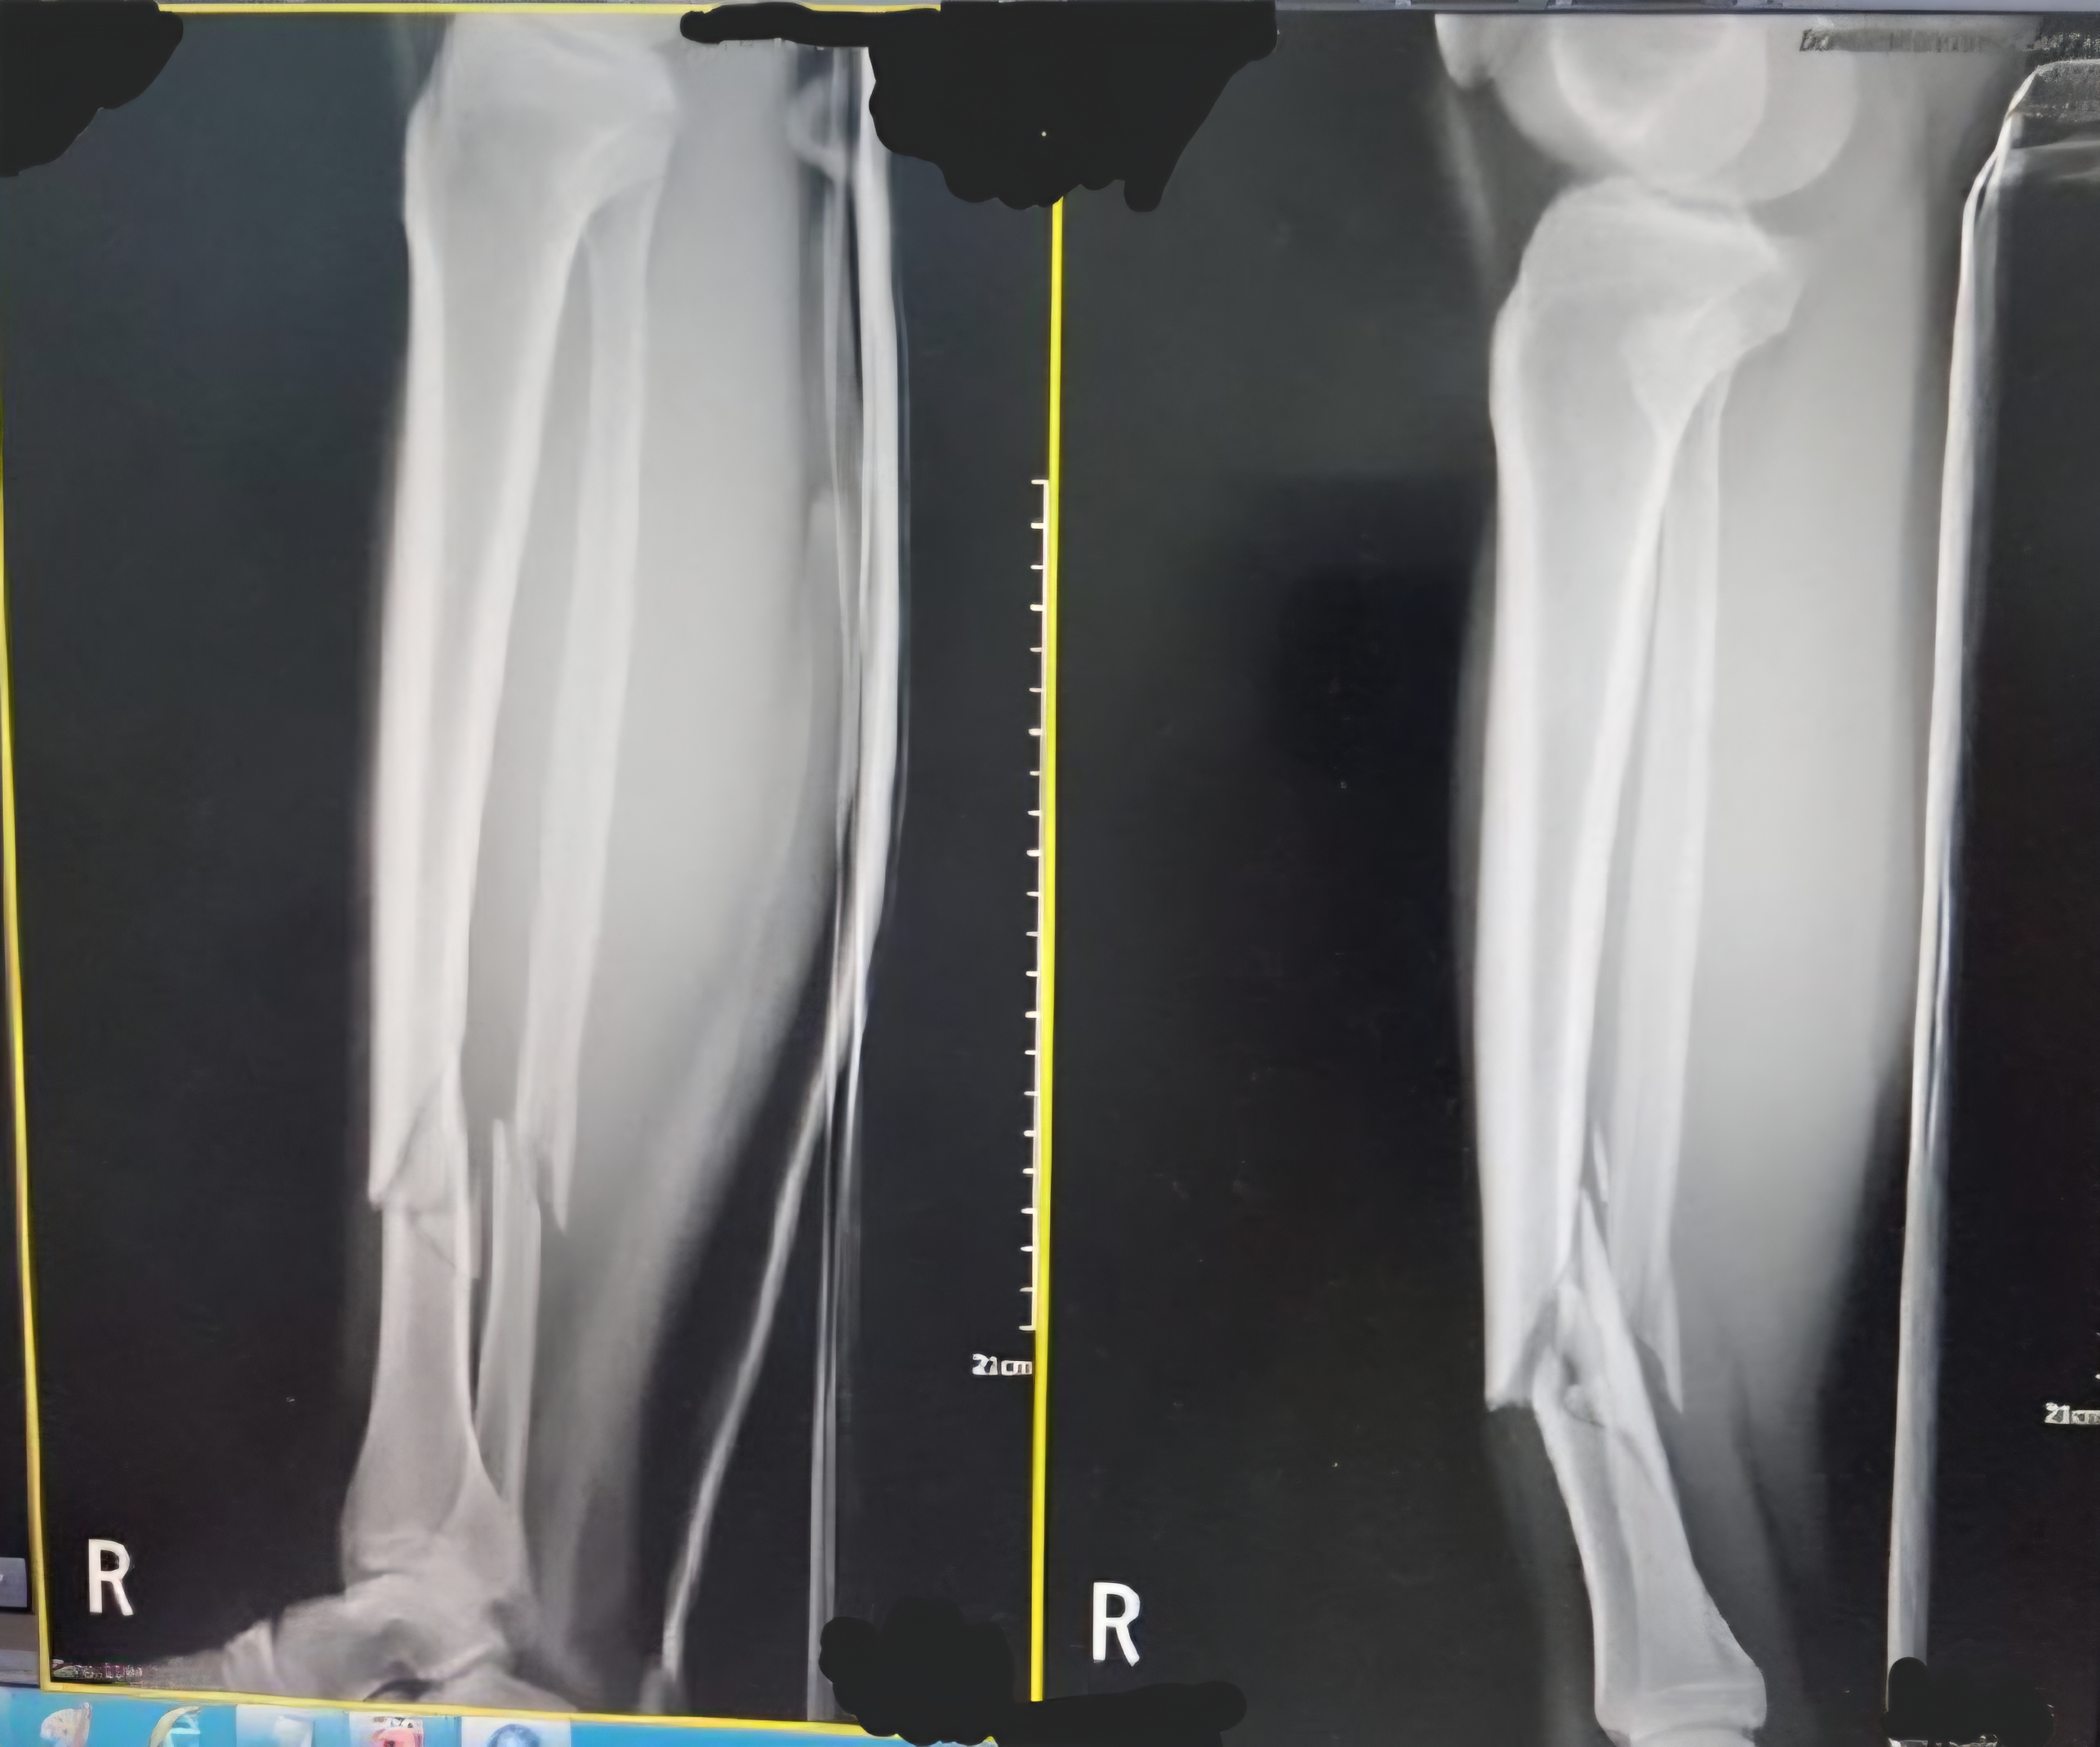

[유머] 멀쩡한 길걷다 발목에 금가는 애 봄 ㅋㅋㅋㅋㅋ [67]

ㅋㅋㅋㅋㅋ 집에서 넘어지니까 이렇게 되더라 반갑다

나도 폰보고 계단내려오다 접질러서 금갈뻔한적 있슨데 암튼 발목 돌아가는거 순식간이니 항상 주의해라

연부조직(인대,근육)들은 괜찮으셔요??

다행히 엑스레이랑 초음파했는데 인대나 다른 건 괜찮데. 멀쩡히 붙으면 핀 안박아도 된데서 다행임 ㅠ | 25.03.26 16:17 | | |

그나마 다행이네요. 뼈보단 연부조직이 회복되어도 기능이 안돌아올 가능성이 있어서 위험한데 뼈만 다치셨다니 회복 잘만되시면 운동능력은 대부분 회복되실 가능성 높겠네요 | 25.03.26 16:22 | | |

길 걷다 다친 거니 지자체 보험 문의나 해봐

블럭이 살짝 어긋나서 올라온거긴 했지만 내 실수라서 뭐... 막 엉망 그런건 아니었음. | 25.03.26 16:18 | | |